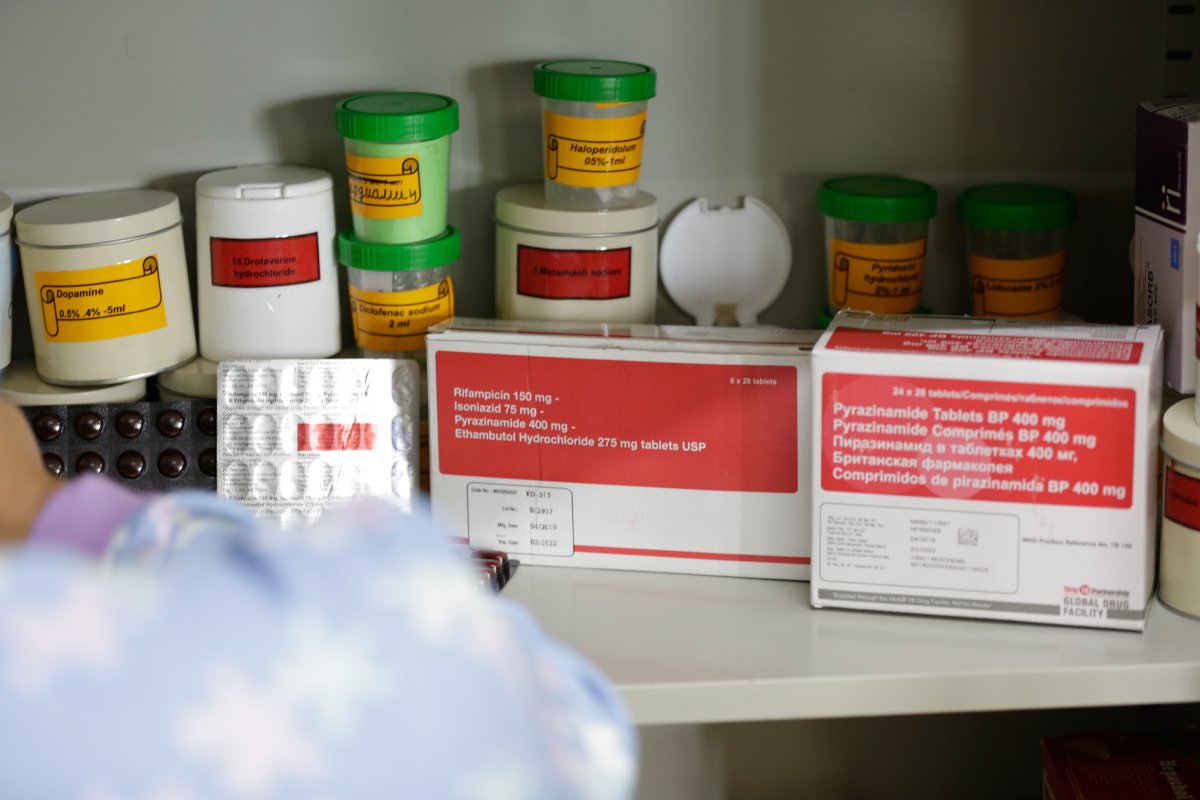

Эмэнд мэдрэг сүрьеэ гэдэг нь эмчийн хяналтаас хамааран 6-8 сарын хугацаанд өдөр болгон тогтмол эм уугаад эмчилж эдгэрэх юм. Нэг ёсондоо, хамгийн анхны хөнгөн хэлбэр гэсэн үг.

Харин эмэнд тэсвэртэй сүрьеэ гэдэг нь хамгийн анхны хөнгөн хэлбэрийн эмчилгээ нь үр дүнгүй болдог эсвэл хүндэрдэг цаашлаад сүрьеэгийн үндсэн эмчилгээнд хэрэглэдэг эмүүд тухайн хүнд үйлчлэхээ болиод эхлэхийг хэлж байгаа юм. Эсвэл тухайн хүн анхдагчаар эмэнд тэсвэртэй сүрьеэгийн нянгаар халдварлагдсан байж болно.

Эмэнд тэсвэртэй сүрьеэгийн эмчилгээний үргэлжлэх хугацаа багадаа 9 сар, дээд талын хугацаа 24 сар байдаг. Өдөр болгон эм уух шардлагатай. Нэг уухдаа тухайн хүнийхээ биеийн жиндээ тааруулаад 12–18 ширхэг хүртэл эм уух шаардлага гардаг. Тиймээс эмэнд тэсвэртэй сүрьеэгийн хувьд олон эм зэрэг уухаар хордлого өгөх тохиолдол гардаг. Байнга дотор муухайрна, хөл гар бадайрч өвдөнө, ядарна, гуйвна, бөөлжинө, гүйлгэнэ. Тэгэхээр эмэнд тэсвэртэй сүрьеэгийн эмчилгээ хийлгэх гэж байгаа хүмүүсээс маш их тэвчээр шаарддаг. Зарим хүмүүс эмчилгээнээсээ халширч, зарим нь тамирдаад ирж чадахгүй, зарим нь хэвтрийн байна, амьжиргааны боломж бололцоо муу зэрэг янз бүрийн шалтгаанаар эмнэлэгт ирж эмээ өдөр болгон ууж чаддаггүй. Тиймээс Эрүүл сүрьеэгүй ирээдүйн төлөө ТББ-аас явуулын баг ажиллуулж, эмэнд тэсвэртэй сүрьеэтэй хүмүүст гэрээр нь очиж өдөр болгон эм уулгаж ,хянах ажлыг хийж байна.

-Сүрьеэгийн эмчилгээ үнэ төлбөргүй гэдэг боловч Засгийн газрын төсөвт суучихсан байдаг. Өөрөөр хэлбэл иргэдэд үнэгүй өгдөг боловч төсвийн мөнгөөр Монгол улс худалдаж авдаг гэсэн үг. Сүрьеэтэй нэг хүнд хийгдэж байгаа зургаан сарын эмчилгээ дунджаар 500–600 мянган төгрөг болдог. Тиймээс бидний зүгээс энэ эмчилгээг үр дүнтэй байлгах тал дээр ажиллахгүй бол болохгүй.

Эмэнд тэсвэртэй сүрьеэгийн эмчилгээ бол бүр өндөр. Нэг эмэнд тэсвэртэй сүрьеэтэй өвчтөнд 1-2 сая төгрөг, эмийнх нь тэсвэржилт нэмэгдээд, хэрэглэж байгаа эм нь өөрчлөгдөөд ирэхээр дахиад 3-4 сая төгрөгийн зардал гарч байна. Өнөөдрийн байдлаар гэрээр зөөж эмчилж байгаа эмэнд тэсвэртэй сүрьеэгийн нэг өвчтөнд 5-17 сая хүртэл төгрөгийг зарцуулдаг. Маш олон эмэнд тэсвэртэй сүрьеэ гэх юм бол 40 сая хүртэл төгрөгийг зарцуулдаг. Энэ их мөнгийг бид Глобал сангийн ДОХ, сүрьеэгийн санхүүжилтээр авч байна. Тиймээс иргэд нэгэнт маш их мөнгө зарцуулж байгаа учраас эмчилгээгээ бүрэн гүйцэд хийлгэх, гэр бүлийнхэн болон хайртай хүмүүсээ болон өөрийн эрүүл мэндийг эрсдэлд оруулахгүй байх нь чухал байна.